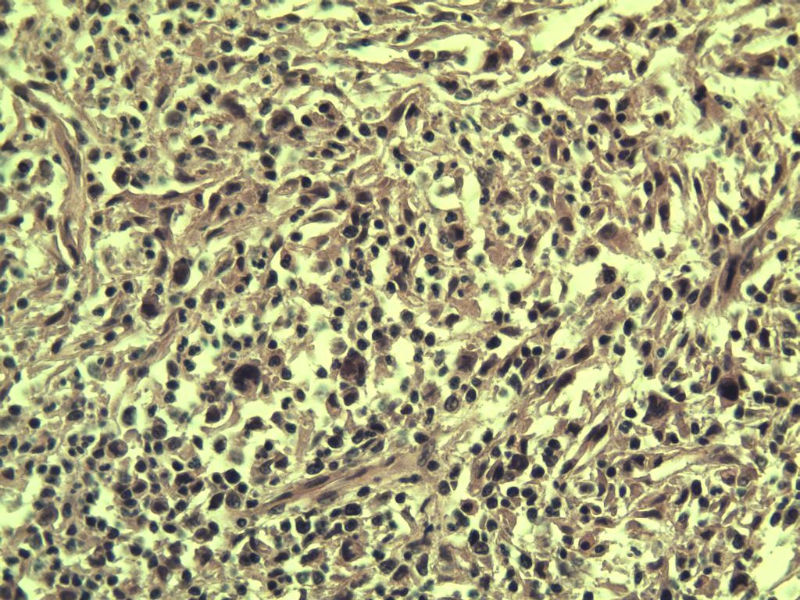

男,38岁,腹股沟 多枚淋巴结活检  直径 0.2-0.5 请各位老师看看 是什么 谢谢了!

"畏寒,发热咳嗽1年,加重伴腹部疼痛2月" 2月前患者感腹部疼痛不适伴大便呈稀大便,量不详,伴腰骶部疼痛,胸片:纵膈及右肺门多发性淋巴结肿大,进一步完善胸部CT:右肺及中叶病变,纵膈及肺门多发淋巴结肿大,结核性可能,脾脏增大,PPD(-),1个月来患者出现中上腹食欲不振,体重进行性消瘦,全身疲乏无力,3天前到医学院就诊,腹部B超:右肝囊肿,胆囊壁毛糙,脾大,胰周多个减弱回声,淋巴结不能除外,腹水,血常规示:WBC16.36x109 /L,N%14.25%,RBC2.63x1012/L ,HGB 66g/L 。右侧腋窝及腹股沟可扪及多枚淋巴结,压痛,无明显粘连。

腹股沟 多枚淋巴结活检图4

副皮质区增生,纤维化显著,细胞呈多形性,有一些多核巨细胞及一些异型细胞,病理性核分裂易见,胞浆红染,散在的小淋巴细胞,T细胞淋巴瘤不能除外,树突细胞肉瘤等鉴别。免疫标记。CD21、CD3、CD5、CD10、CD20、CD79a、PD1、CD68、CXCL13、KI-67、CD68、CD163等,据切片选择。不知对否。

淋巴结正常结构破坏,可见大的异型细胞,上皮样或梭形,恶性肿瘤,依据病史,首先考虑淋巴造血系统疾病,大中小细胞混杂,大细胞多,形态多样,可见多核瘤细胞,除以上考虑外需鉴别间变大、组织细胞肉瘤、指状突/树突细胞肿瘤、HL等,还需排除肉瘤或癌转移,尽管病人年轻,加上ALK、CK、S-100、CD1a。